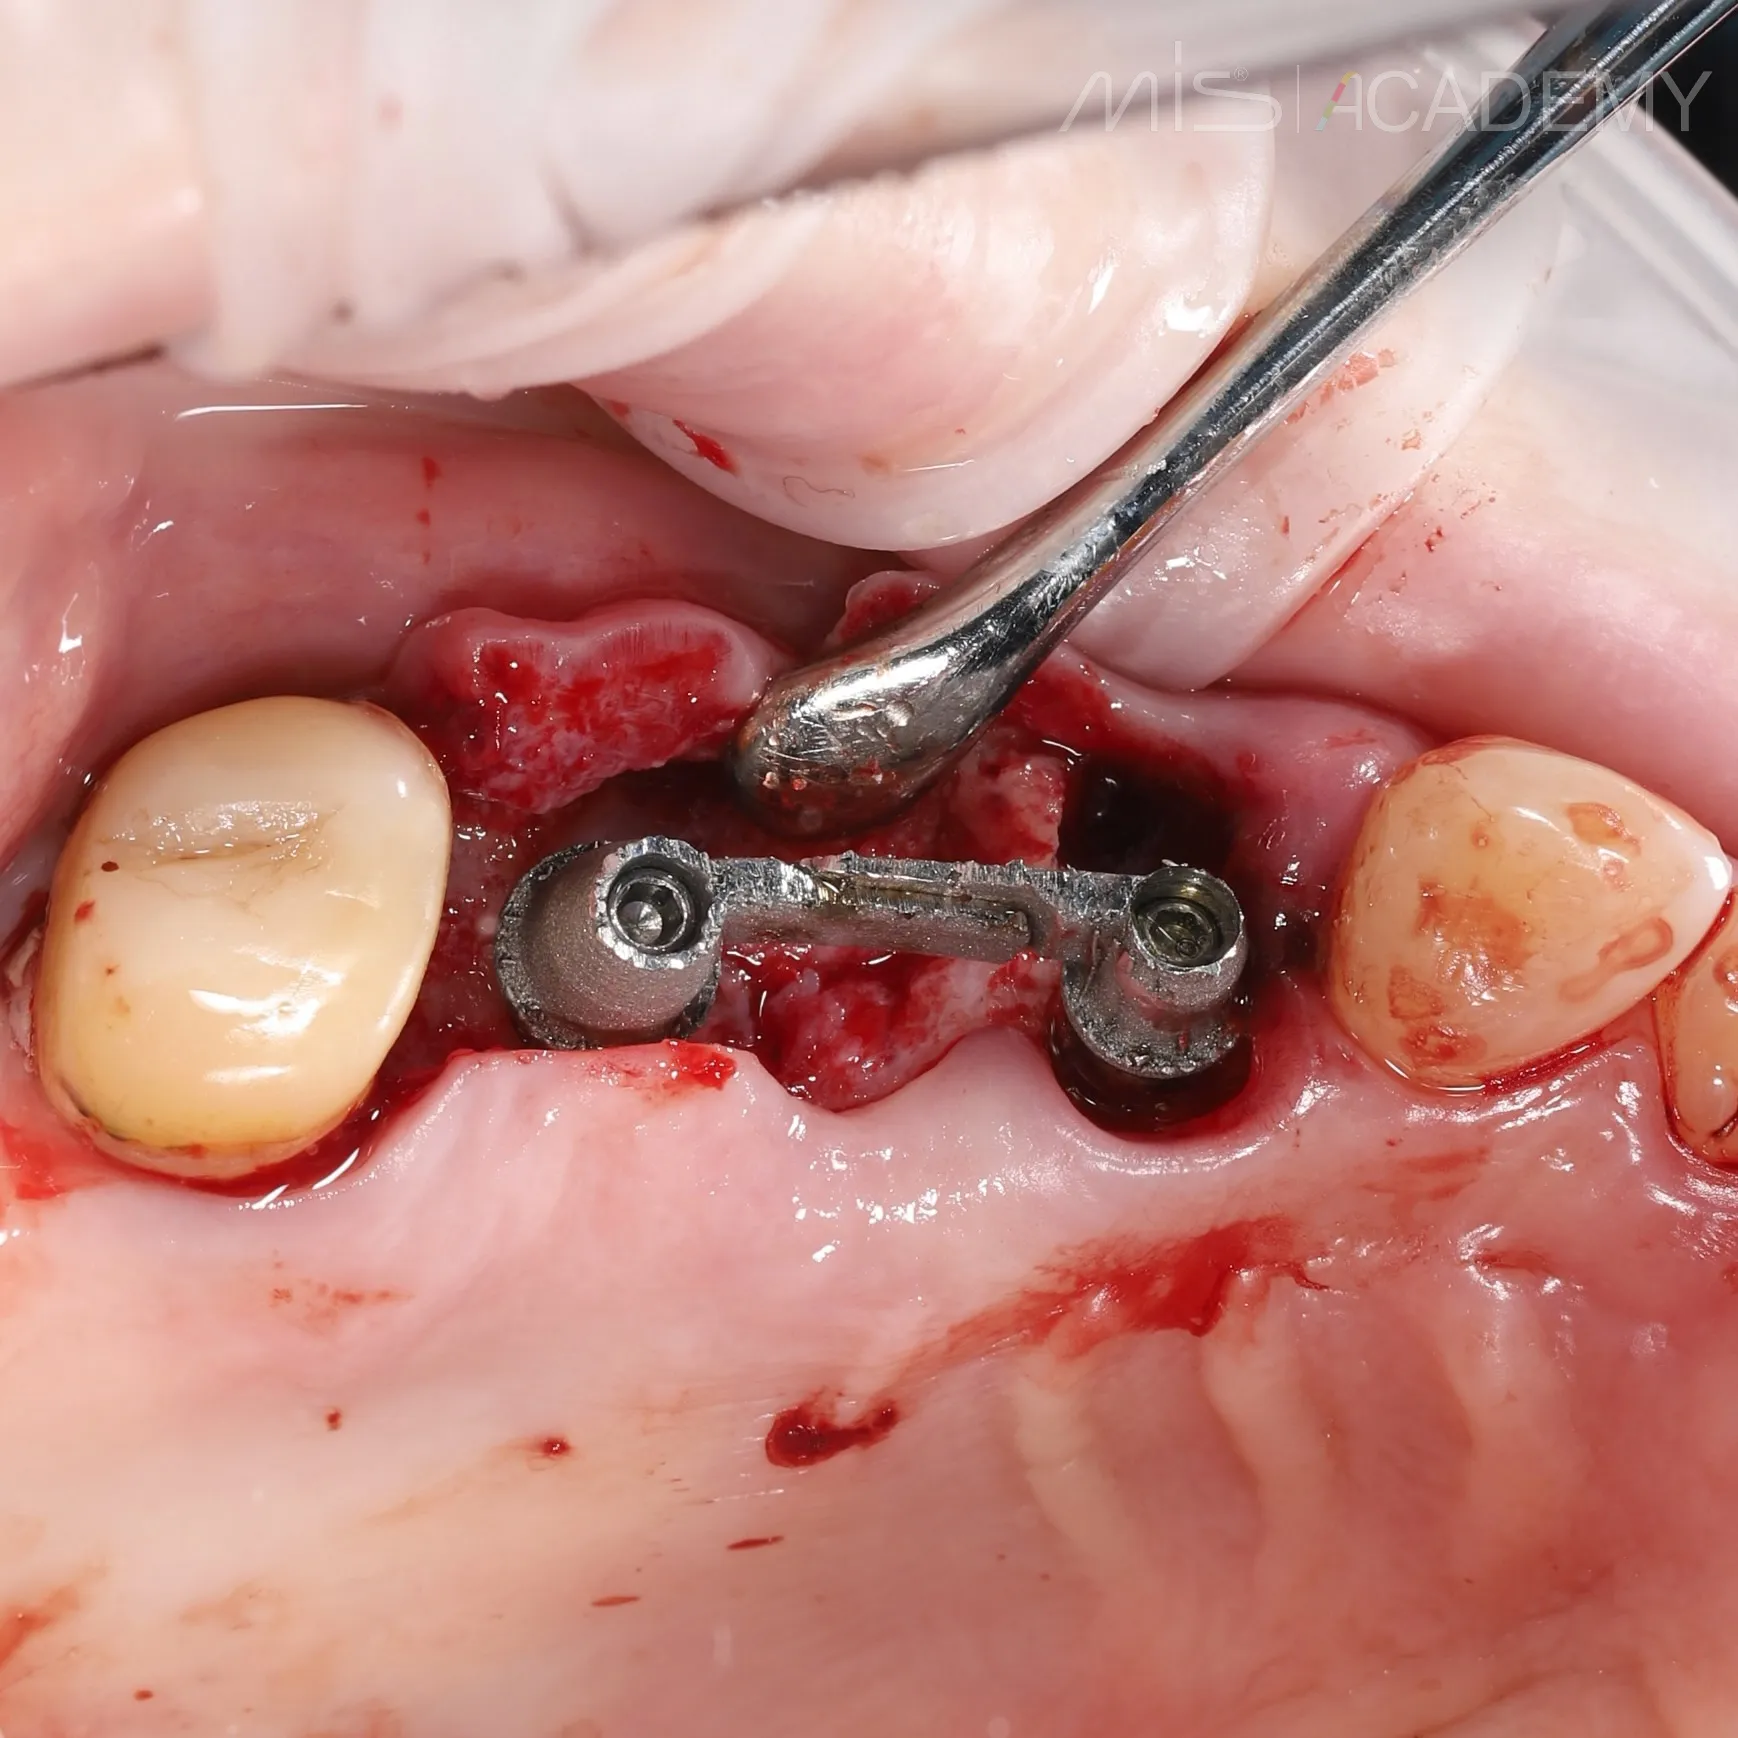

— Импланты MIS C1 3.75×13 и 4.2х8.

— Установлены multi unit в области 2.6.

— Connect- абатмент в области 2.4.

— Фиксация балки lego bridge + внутриротовая сварка.